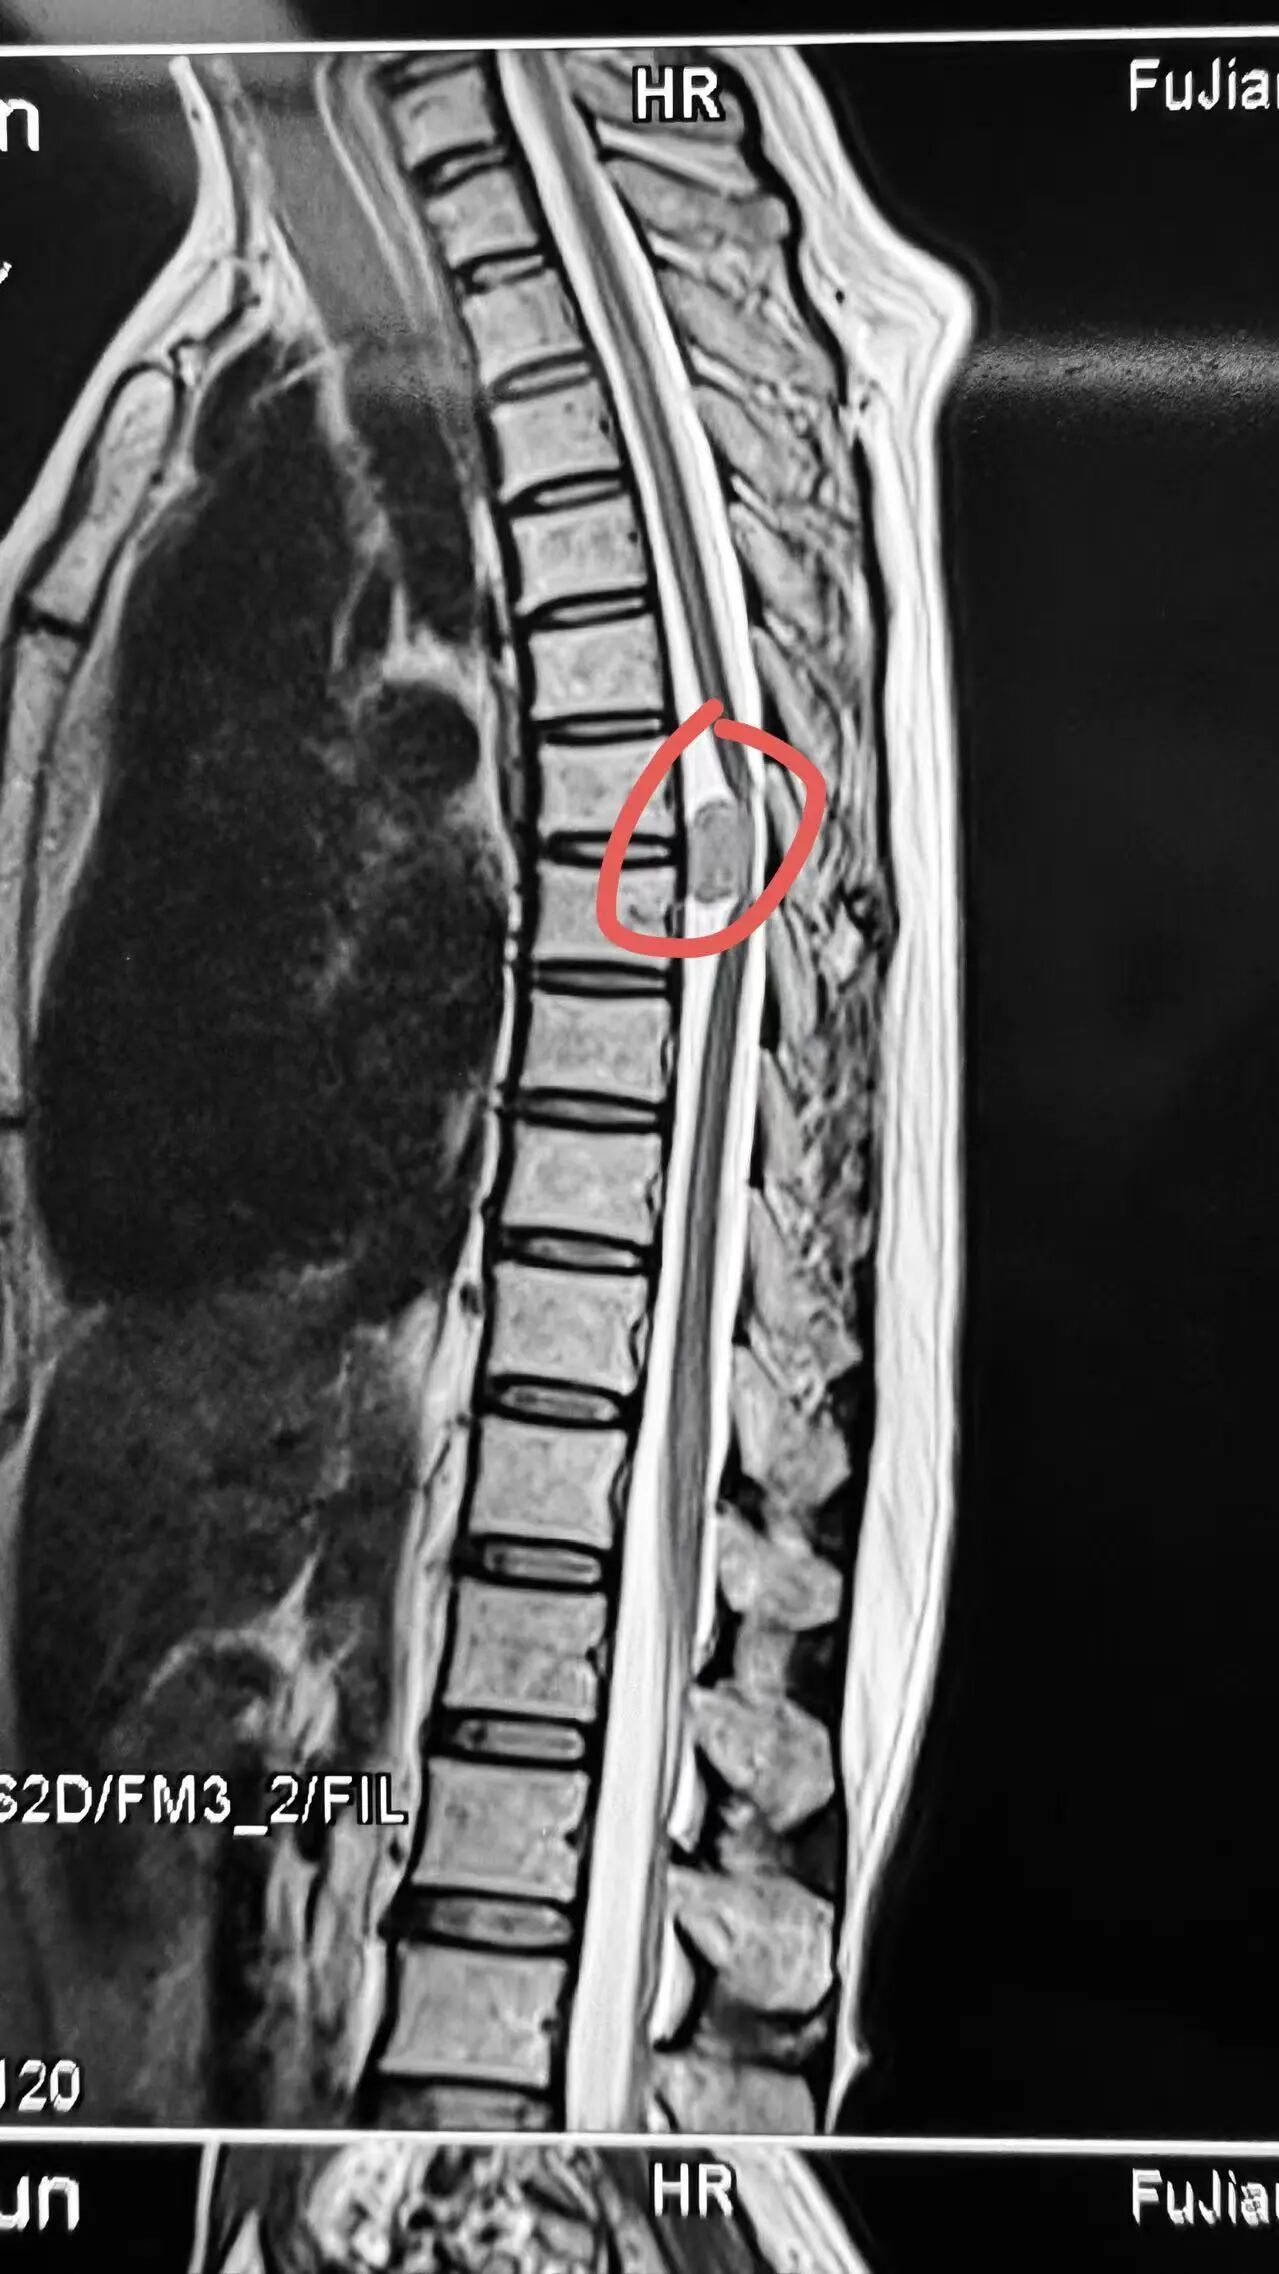

林女士因双腿急剧加重的麻木无力几乎瘫痪,需人搀扶才能勉强移动。影像检查显示,其胸椎椎管内长有一肿瘤,且位置极为凶险——正处于脊髓的腹侧(正前方),严重压迫中枢神经通道。

肿瘤位于脊髓的腹侧

“脊髓腹侧肿瘤是脊柱外科手术中风险最高的类型之一,”徐杰教授指出,“胸椎椎管空间狭窄,传统手术必须牵拉脊髓才能抵达前方病变,术中极易造成脊髓损伤,导致永久性功能障碍。”